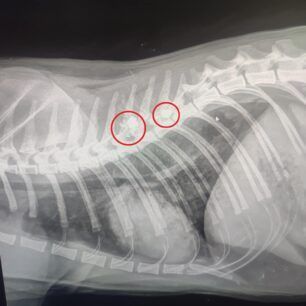

Το ζώο, όπως έδειξαν οι ακτινογραφίες, είχε πυροβοληθεί με αεροβόλο δύο φορές. Το ένα σφαιρίδιο είχε καρφωθεί στην σπονδυλική του στήλη και αν δεν είχε πάει επί τόπου ο εθελοντής διασώστης Κώστας Μαμασούλας, ώστε και να το πιάσει και να το μεταφέρει σε κτηνιατρική κλινική, η γάτα θα ήταν ήδη νεκρή και θα είχε μαρτυρικό θάνατο…

Οι πιθανότητες να περπατήσει είναι λιγες, ωστόσο αποφασίστηκε να κάνει το χειρουργείο και να του δώσουμε έστω αυτή την μικρή πιθανότητα ώστε να βγει η σφαίρα που είχε σφηνώσει στην σπονδυλική στήλη και να αποσυμπιεστεί. Τώρα το μόνο που μας μένει είναι να περιμένουμε, καθώς είναι πολύ δύσκολο ζώο και καθόλου συνεργάσιμο.».